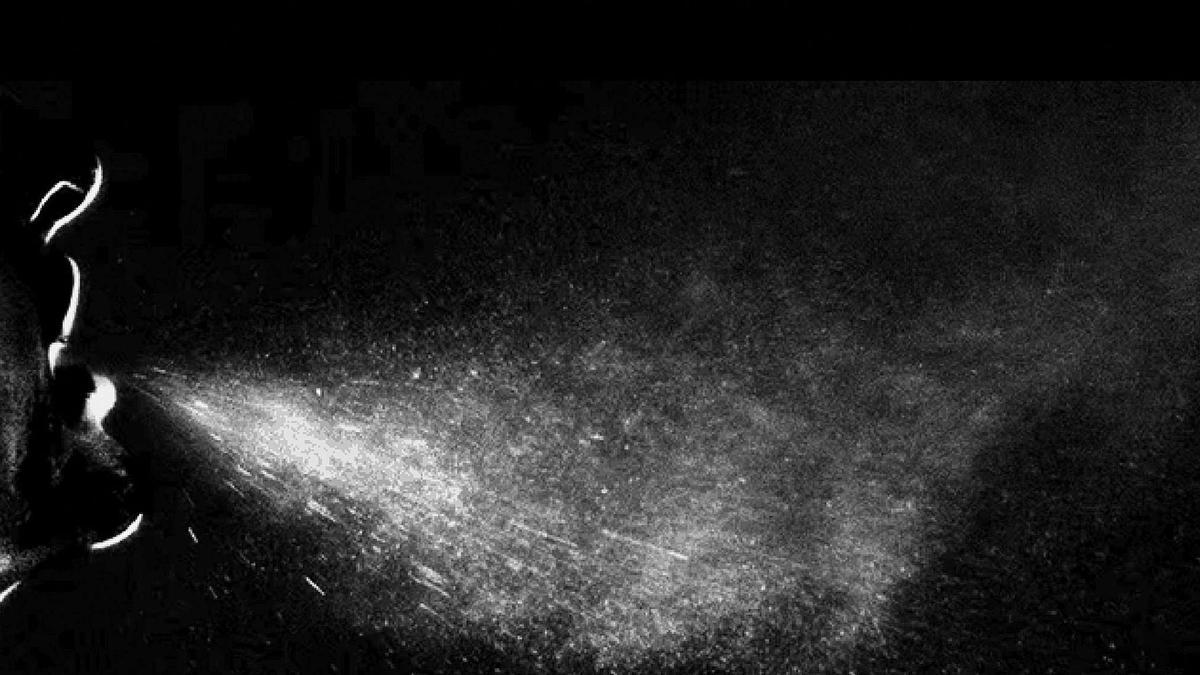

El documento incide en la “importancia” de explicar a la población el papel de la transmisión aérea. En este sentido, explica que al respirar, hablar, gritar, toser o estornudar se emiten abundantes partículas: gotículas y aerosoles. Las gotículas infectan por impacto en los ojos, fosas nasales o boca, y caen al suelo hasta a 1-2 metros de la persona que las emite mientras que los aerosoles infectan por inhalación y viajan más de 1-2 metros antes de caer al suelo. Precisa que los aerosoles presentan una mayor infectividad porque penetran más profundamente en los pulmones y, además, podrían causar una mayor gravedad en la enfermedad. Esa infección “anisotrópica” se observa en la gripe, en la que la dosis infectiva con síntomas similares es 100.000 veces mayor por deposición en la nariz que en los pulmones y también se observó en la viruela.